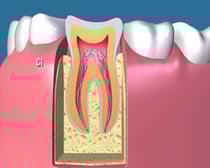

健全歯:

健全歯

何も虫歯のない、健康な歯の状態です。